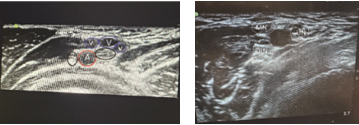

Figure 4. Ultrasound findings of supraclavicular brachial plexus block: pleura, first rib, SA- subclavian artery, and PB – brachial plexus posterolateral to the artery. The first image shows a US scan on a 2-year-old patient and the second an 11year old patient. The red line is directed on the “corner pocket”

Anatomy and ultrasound characteristics. At the level of the axillary block, the median, ulnar and radial nerves are blocked. The target nerves are located in variable positions around the axillary artery, due to frequent anatomical variations (Fig. 7). The linear probe is placed in the axilla, and the target nerves are located around the anechoic axillary artery (Fig. 6 and 7). The median nerve usually lies superficially above the artery; the ulnar nerve is commonly located superficial and medial to the artery; whereas the radial nerve lies under and medial to the artery. The musculocutaneous nerve appears as a hyperechogenic oval structure between the coracobrachialis and biceps muscles. It needs to be blocked when tourniquet is applied.

Figure 7. Ultrasound findings of axillary block: A- axillary artery, V – veins, MN – medial nerve, UN – ulnar

nerve, RN – radial nerve. The first image is of a 7-year-old patient where the ulnar and medial nerves are located medially from the artery and the radial nerve is lateral to the artery. The second image is of a 15-year-old child with a different position of the nerves compared to the previous one.